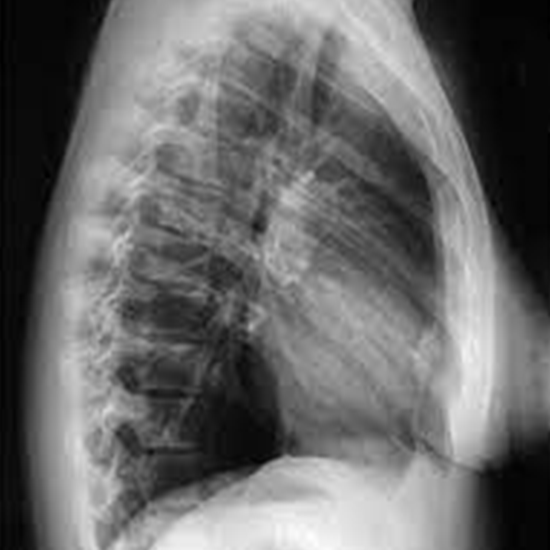

The lateral sternum is a cross-sectional x-ray view of the whole length of the sternum. The view is used to ask questions about fractures or infections.

A sternum X-ray is used to see the sternum (also known as the breastbone) and the surrounding soft tissues.